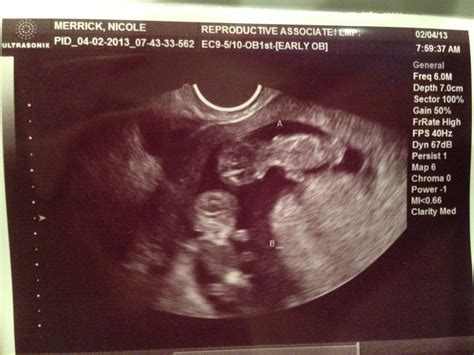

10 Week Ultrasound Twins

The 10 week ultrasound twins scan is typically performed between 9 and 11 weeks of pregnancy. This early ultrasound is essential for several reasons, including confirming the presence of twins, assessing the gestational age, and evaluating the overall health of the fetuses. During this scan, the ultrasound technician will use high-frequency sound waves to create images of the uterus and the developing twins.

During the scan, the technician will look for several key indicators:

• Heartbeat: The presence and strength of the heartbeats in both twins.

• Gestational Age: The size and development of the fetuses to confirm the gestational age.

• Placenta and Amniotic Sacs: The location and health of the placenta and the presence of separate amniotic sacs.

• Fetal Pole: The presence of the fetal pole, which is the earliest visible sign of the embryo.

• Yolk Sac: The yolk sac, which provides early nutrition to the embryo.

• Crown-Rump Length (CRL): The measurement of the length of the fetus from the top of the head to the bottom of the buttocks, which helps in determining the gestational age.

Additionally, the scan may reveal the presence of the amniotic sacs and the placenta. The position and health of these structures are crucial for the twins' development.